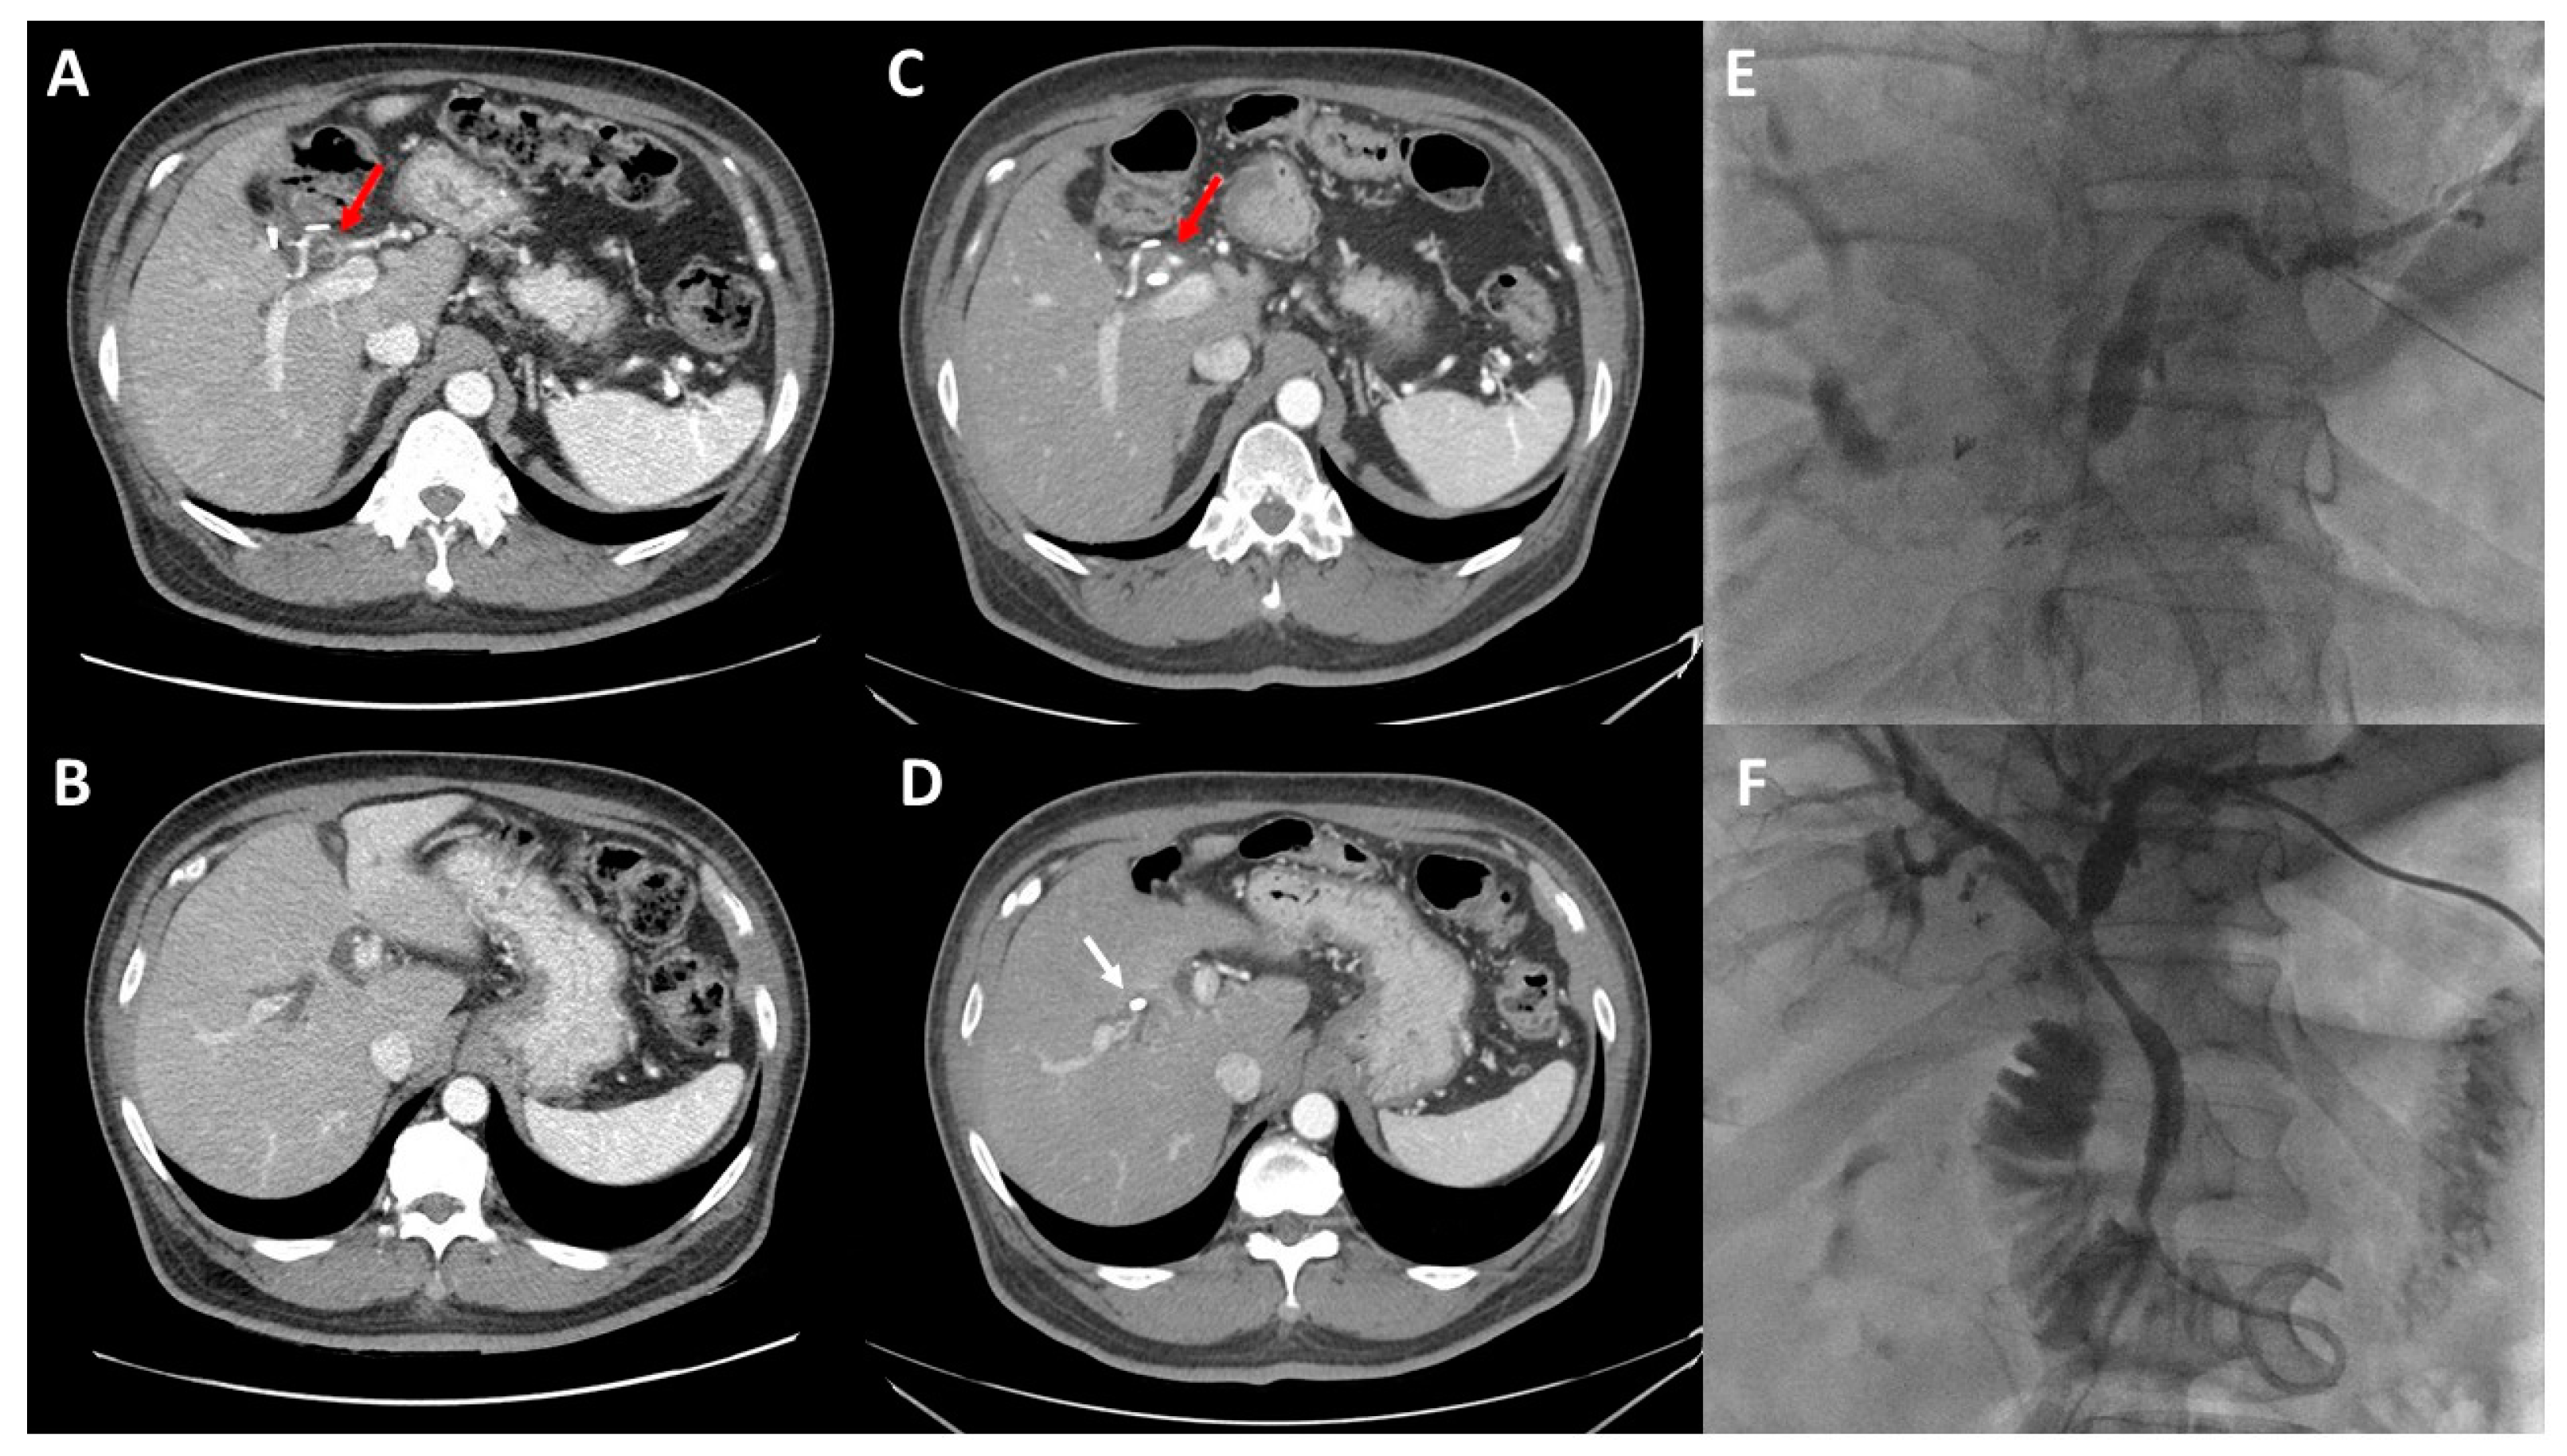

2. Preoperative Imaging

5. Volumetric Analysis and Optimization